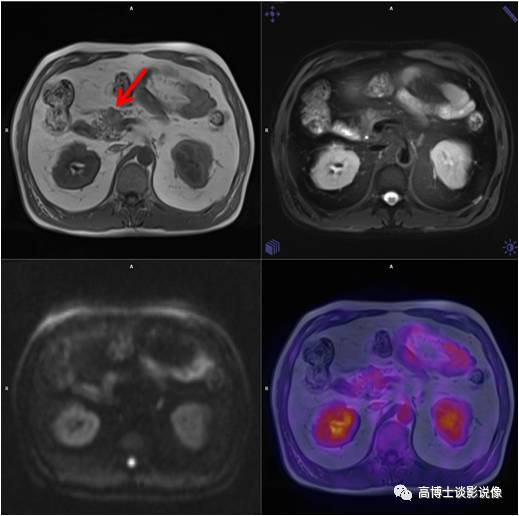

肾癌

老年女性,右下肢胀半年余,右侧卵巢良性肿瘤术后。右肾上部见一长径约4.5cm肿块,FDG呈本底摄取。手术病理“肾癌”。

点评

肾癌约占成人恶性肿瘤的2%~3%,近年来,约50%的肾癌是经健康查体时发现的无症状肾癌。有症状的肾癌患者中最常见的症状是腰痛和血尿。对早期肾癌患者可采用微创的保肾手术,对中晚期肾癌患者则采用根治性肾切除术,因此早期发现非常重要。

血管平滑肌脂肪瘤

中年女性,甲状腺肿瘤术后复查。右肾中部见直径约2.5cm异常信号灶,内含脂肪信号,FDG无代谢,诊断为血管平滑肌脂肪瘤。

血管平滑肌脂肪瘤(以往称错构瘤)是肾良性肿瘤中最常见者,约占肾肿瘤的3%。肿瘤较小者,可以B超定期随访复查;巨大的肿瘤会压迫邻近脏器,且容易发生出血,引起腹痛等急症,应避免剧烈运动及外伤。